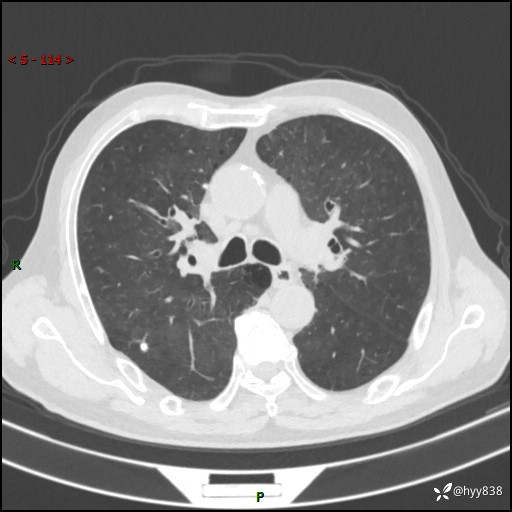

辅助检查:CT

胸部CT平扫